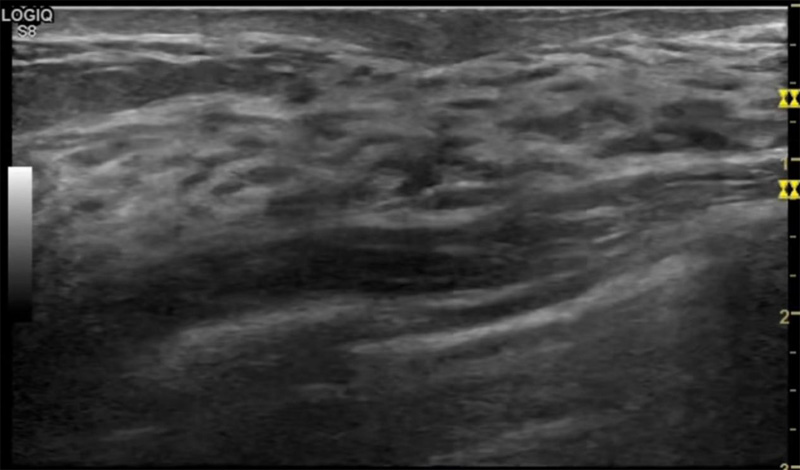

乳房脹痛,觸摸疼痛,手摸起來感覺有腫塊。這個是什么問題呢?醫(yī)生診斷一般是乳腺增生。那么在乳腺超聲設備檢查后,報告單卻顯示雙乳未見明顯占位性病變。乳腺增生是很多女性,特別是育齡期女性都有的經(jīng)歷、到底乳腺增生癥狀有哪些?會給我們帶來怎樣的影響呢?乳腺增生不是腫瘤跟炎癥。乳腺組織增生及退行性變跟內分泌功能紊亂有關系。正常的生理改變。還有乳腺病,良性乳腺結構不良等名稱。

乳腺增生有什么癥狀,病因?比較典型的就是乳房疼痛,特別是經(jīng)前癥狀比較重,經(jīng)后就有所緩解。有時候還能碰到乳房硬塊。根據(jù)經(jīng)期的變化而變化硬度大小都有變。乳腺在內分泌激素,伴隨月經(jīng)周期有增生問題。內分泌激素代謝失衡,雌激素水平增高,出現(xiàn)乳腺組織增生過度,增生組織不退的情況下,就會有乳腺增生癥狀。這個不會增加乳腺癌的風險。所以不用緊張的。不過乳腺癌的病人都會有乳腺增生。所以乳腺增長有沒癥狀,都需要進行常規(guī)的體檢。